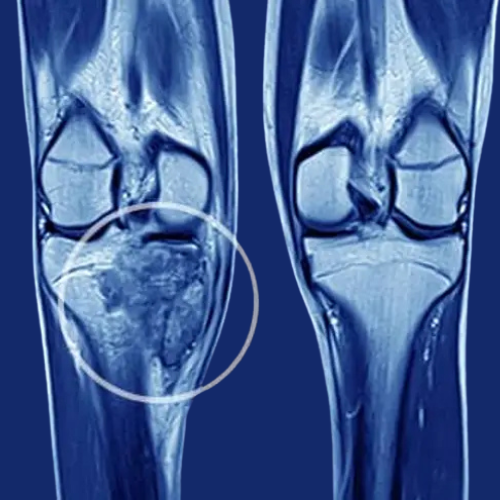

Knee Replacement Surgery

Knee replacement surgery is a procedure where a damaged knee joint is replaced with an artificial titanium implant to relieve pain and improve mobility. It helps patients regain normal knee function and enhances quality of life.

knee-replacement-surgery.

Vision by group College was established in of dedicated people to provide made medical education